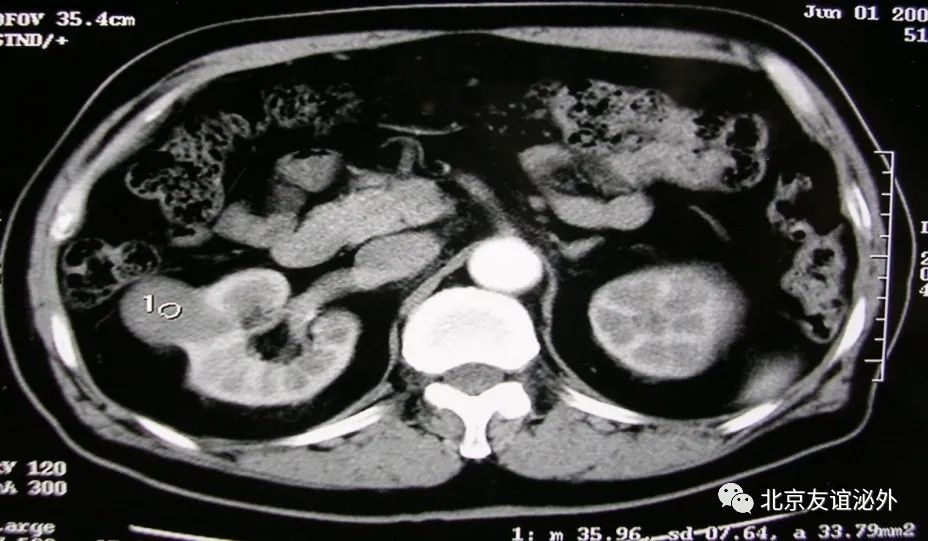

图2. Bosniak I级恶性囊肿(肾透明细胞癌),临床极为少见